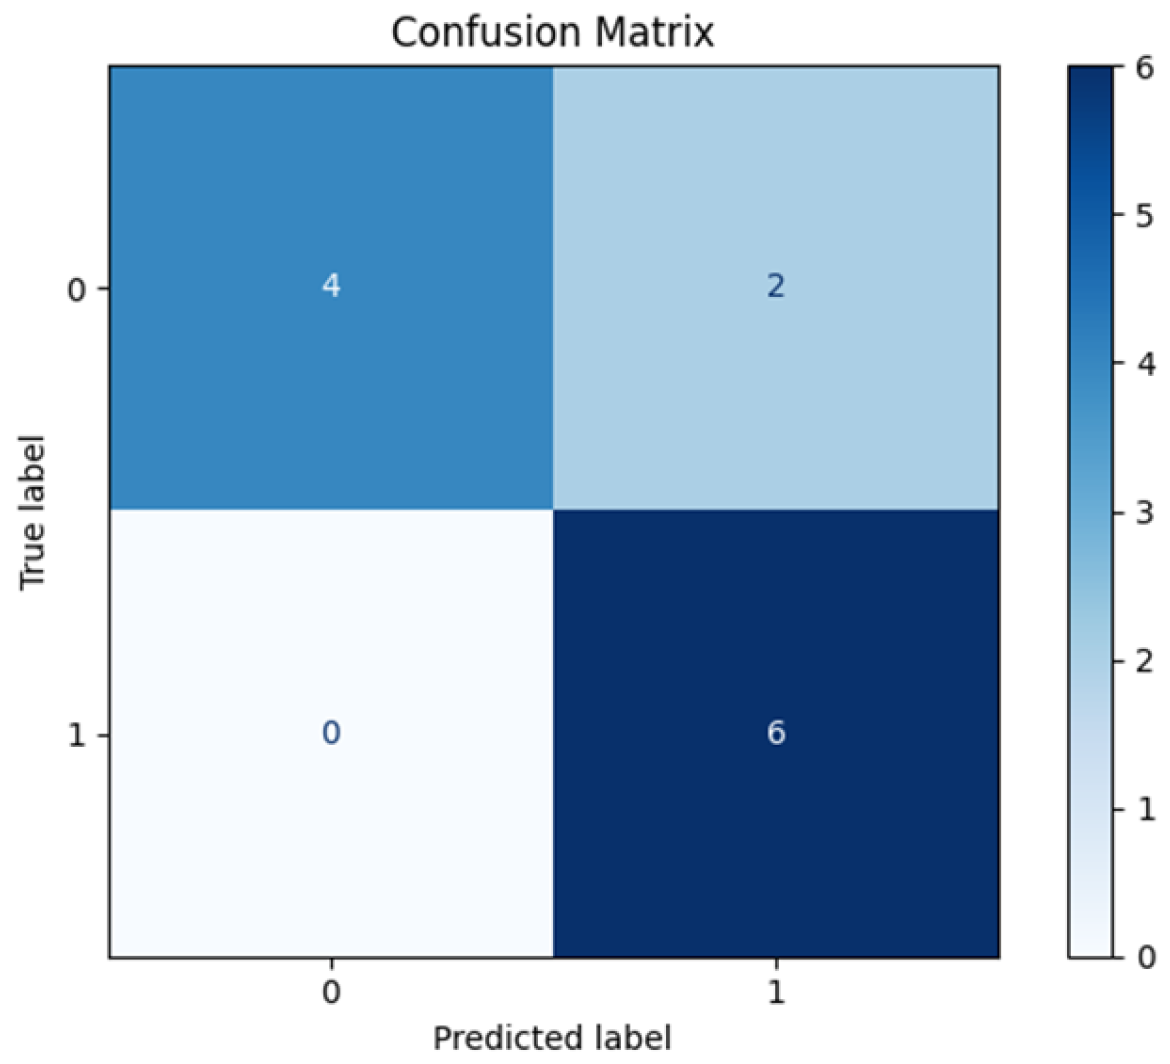

3.1. Leave-One-Patient-Out Cross-Validation (LOPO-CV)

| #Metric | Mean Value | CI |

|---|---|---|

| Accuracy | 0.83 ± 0.11 | 0.58–1.00 |

| Sensitivity | 1.00 ± 0.00 | 1.00–1.00 |

| Specificity | 0.66 ± 0.21 | 0.20–1.00 |

| PPV | 0.75 ± 0.15 | 0.42–1.00 |

| NPV | 1.00 ± 0.00 | 1.00–1.00 |

| ROC-AUC | 0.80 ± 0.14 | 0.47–1.00 |

| PR-AUC | 0.83 ± 0.14 | 0.49–1.00 |

| Brier score | 0.18 ± 0.05 | – |